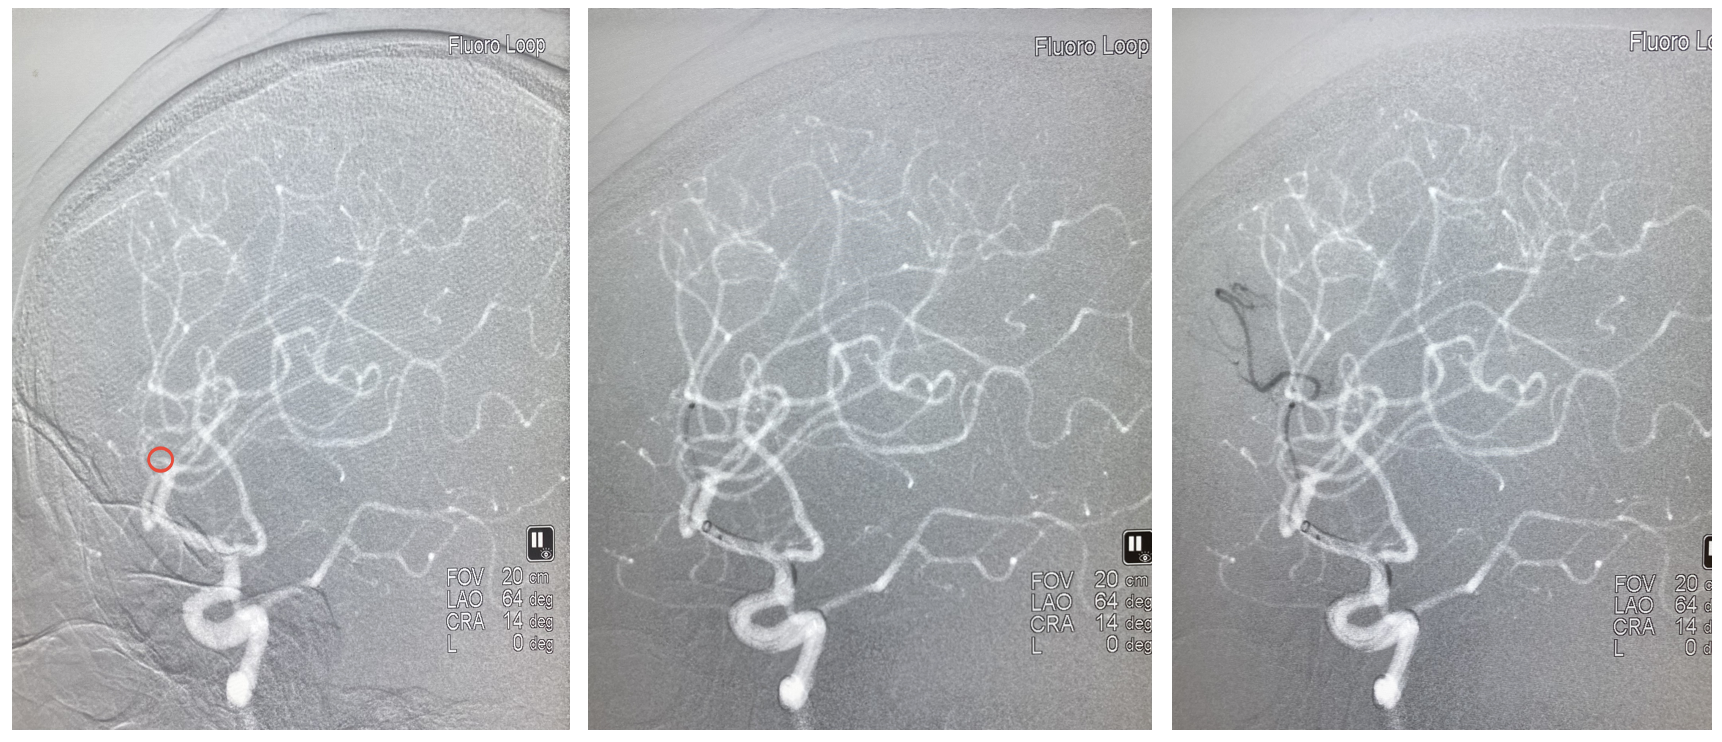

4、给予替罗非班后为进一步了解病变,行3D造影,最终证实M2分叉部一共有4支,开通3支,还有1支闭塞,指向额叶供血。

5、工作位路图,在中间导管高到位辅助下微导管超选M2闭塞分支,冒烟证实血管真腔,释放心玮4-20取栓支架。

6、关闭滴注,中间导管到达M2分叉部,缓慢轻拉支架入中间导管整体撤出体外,可见支架远端附着血栓。 术后即刻造影,闭塞分支血管再通,M2闭塞处的可疑血栓消失,至此4支血管全部通畅,血流3级,结束手术。